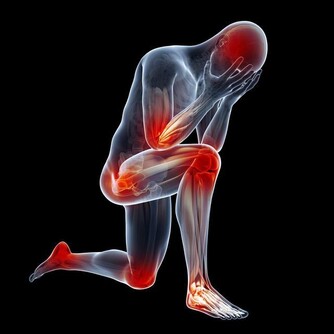

4、全身疼痛——缺乏維生素D 曬太陽不足、或維生素D缺乏的人,就容易引起慢性疼痛,加上維生素D是人體無法自行合成的營養素,補充更為重要。維生素D也是促進骨骼生長、牙齒健全的重要物質。

來源:每週吃2份油性魚類如鮭魚、沙丁魚等,再加上適時曬點日光才能保證體內有充足維生素D。